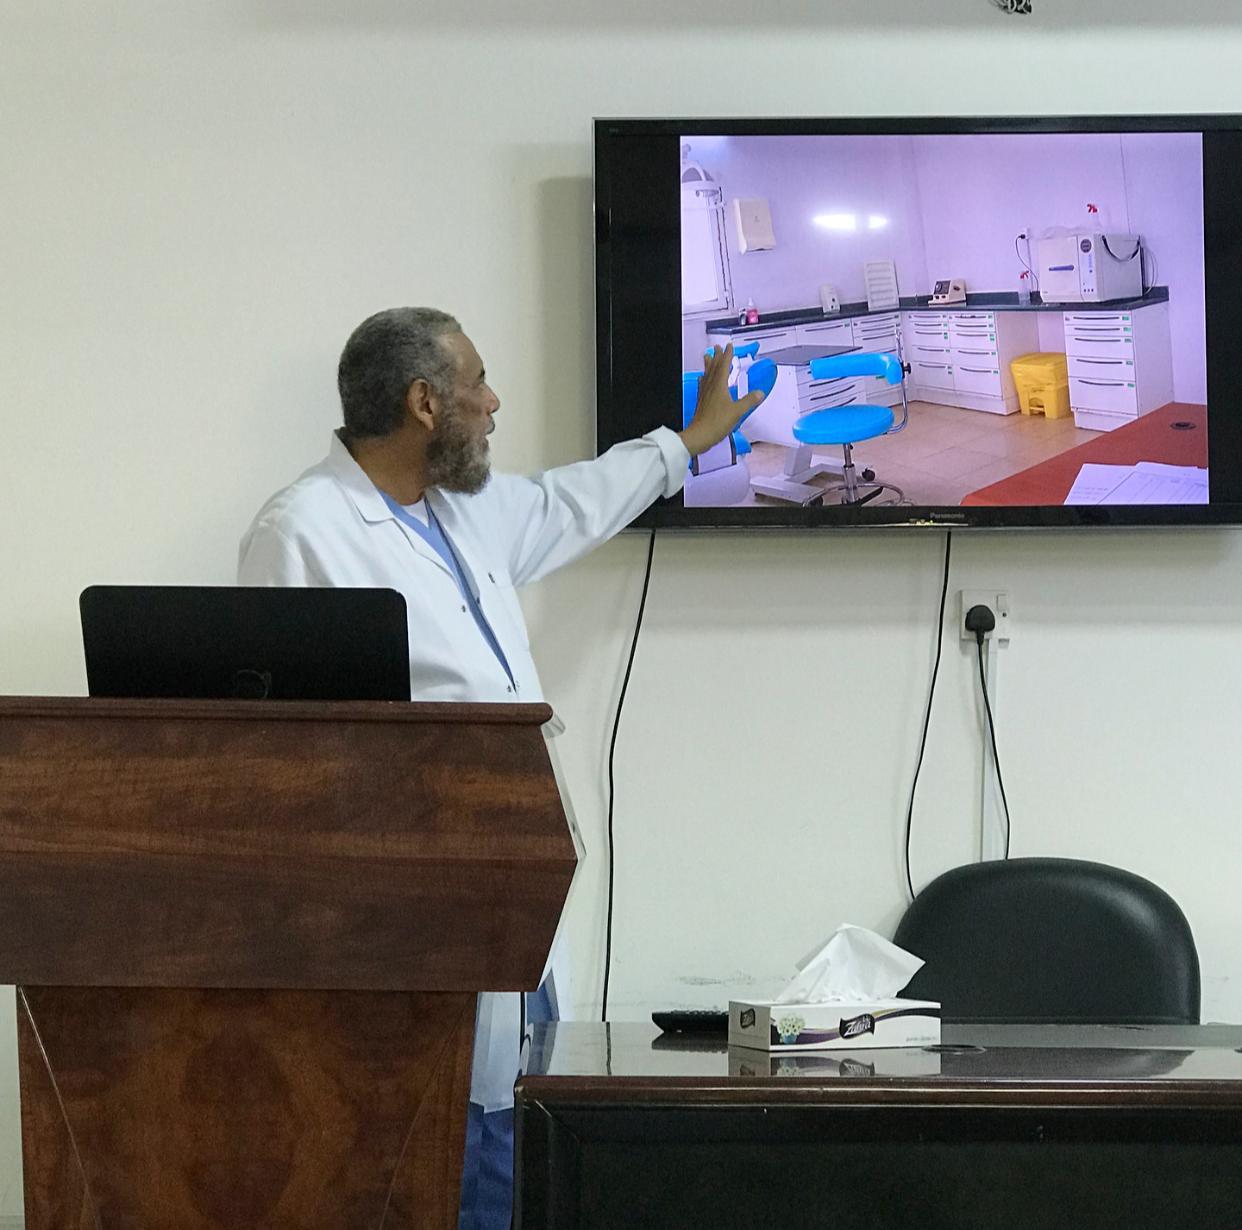

![]()

تسوس الأسنان